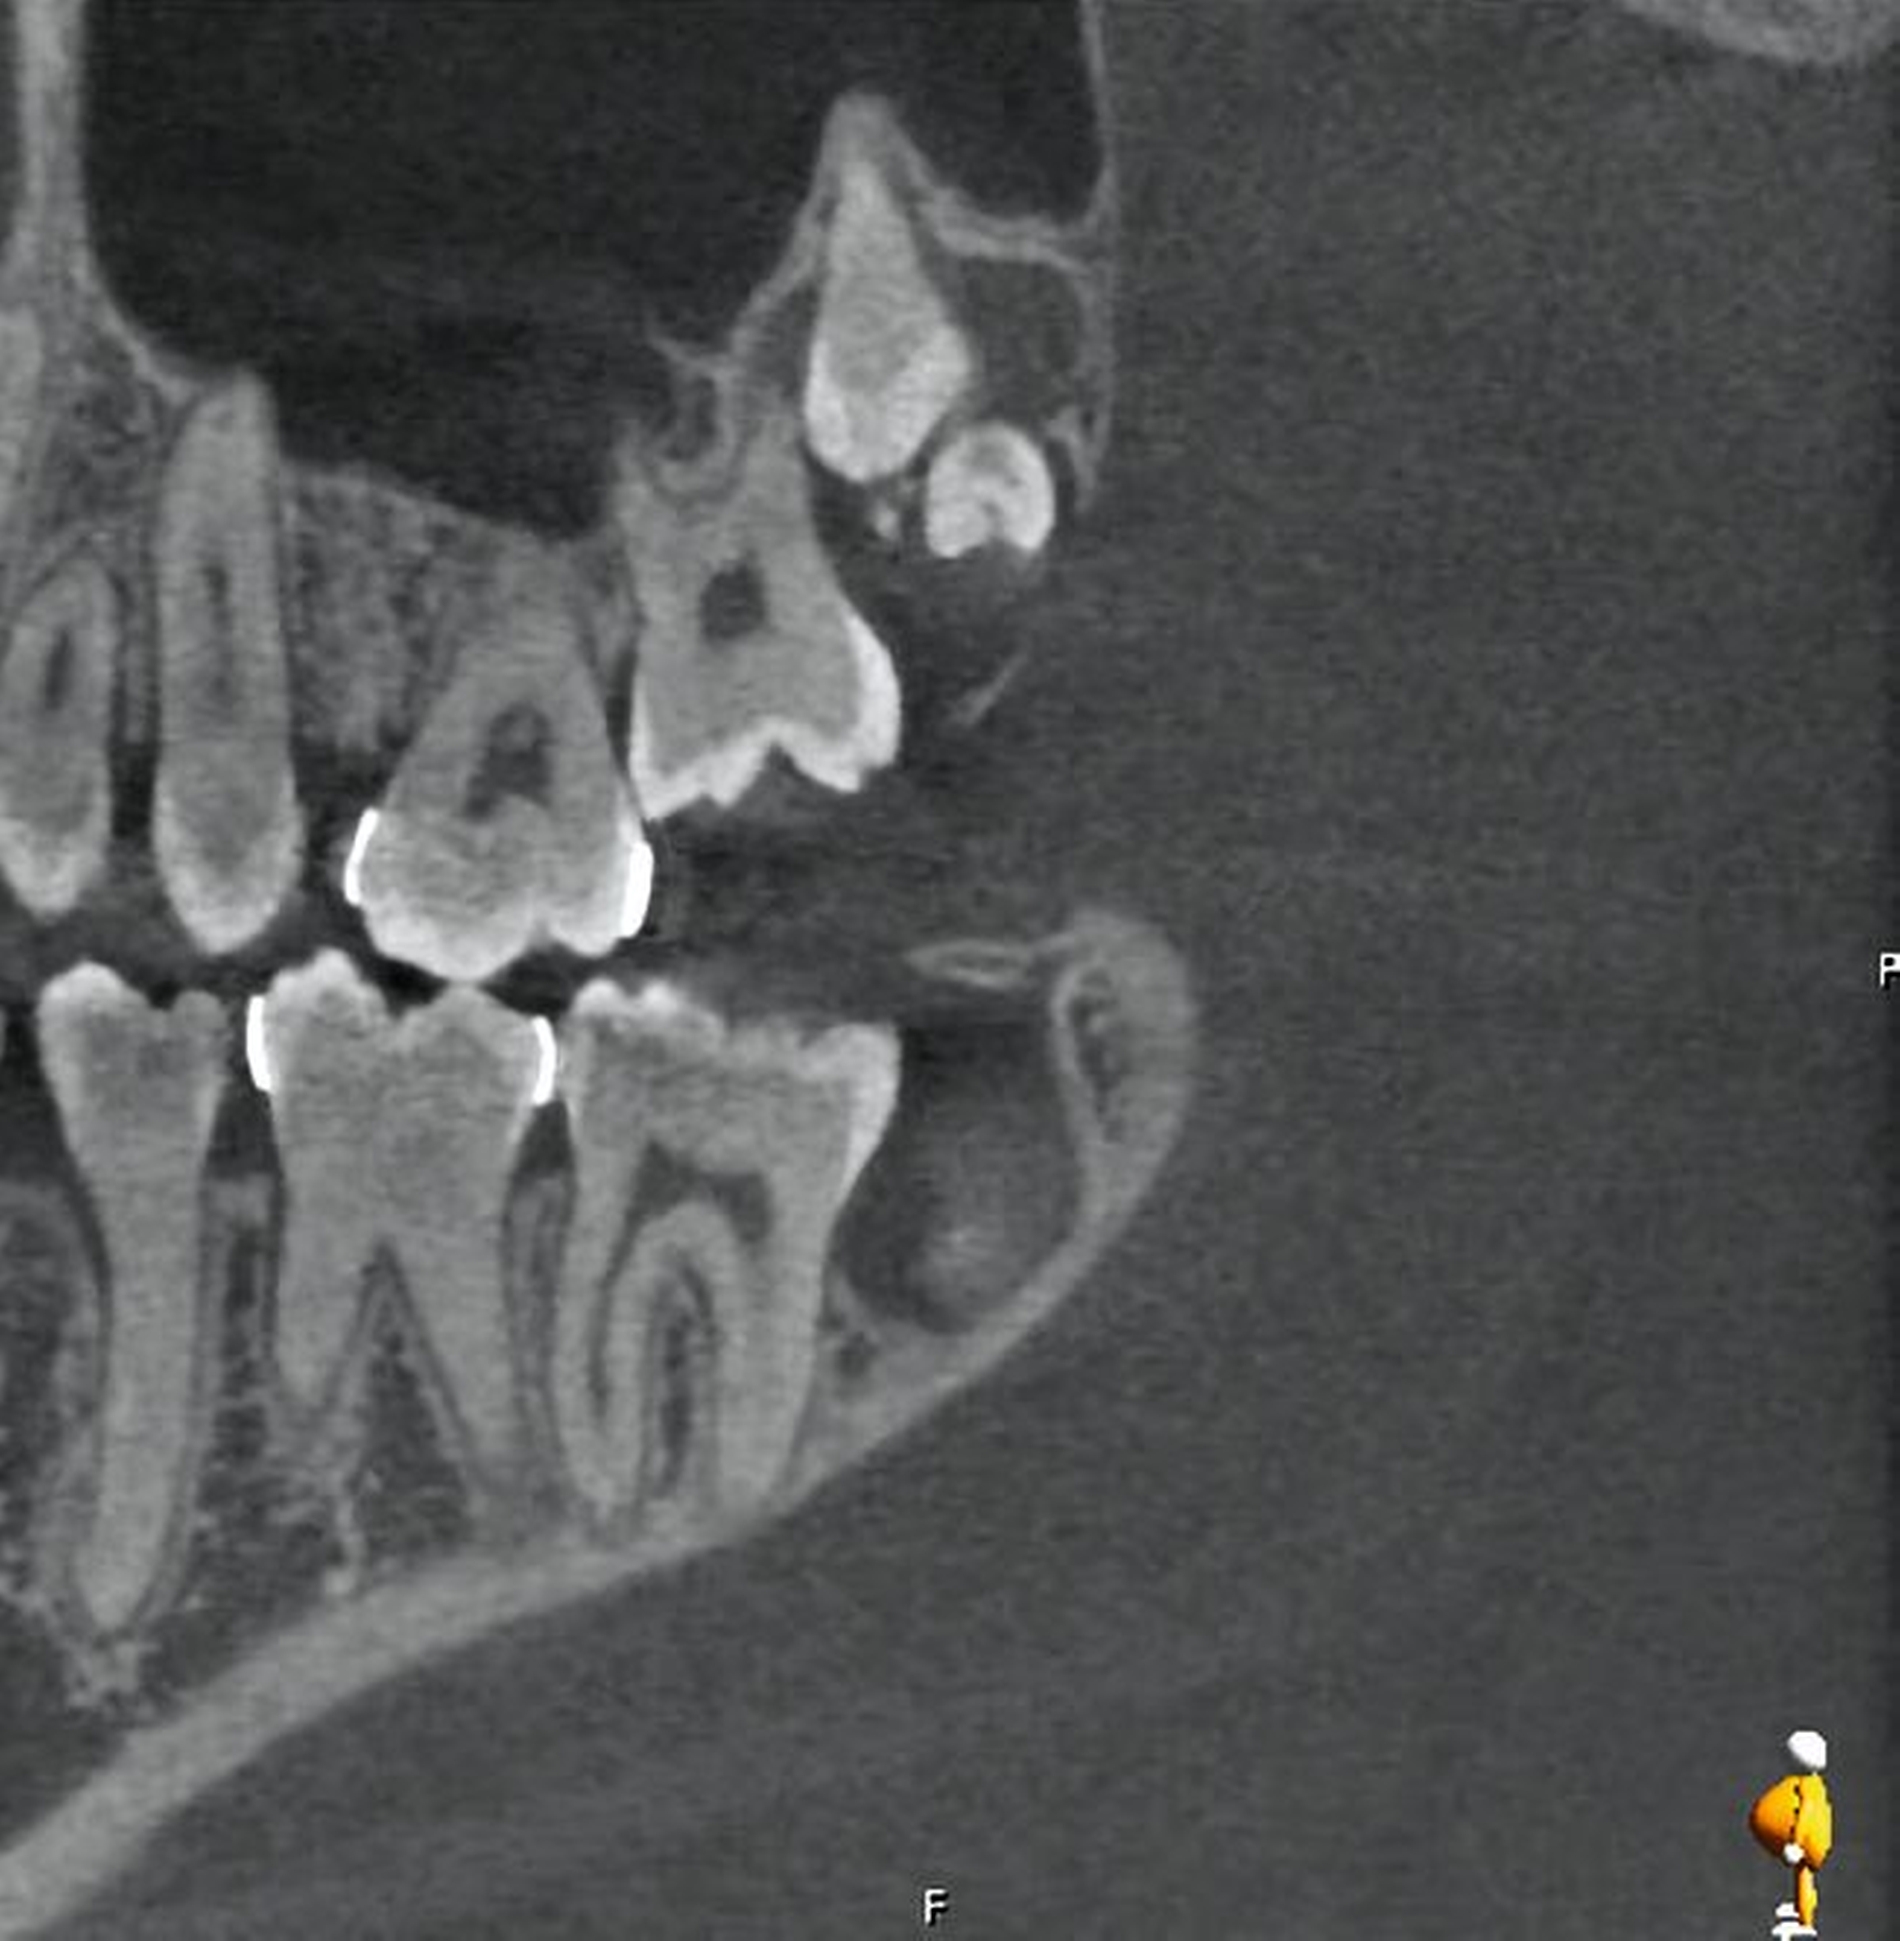

Im Oberkiefer zeigte sich auf der linken Seite neben dem hoch verlagerten und retinierten Zahn 28 ein ebenfalls hoch verlagerter und retinierter Zahn 29 (Abbildung 4) mit enger Lagebeziehung zur Kieferhöhle. Im rechten Oberkiefer erkennt man neben dem hoch verlagerten und retinierten Zahn 18 eine Doppelanlage des Zahnes 19 ebenso in enger Lagebeziehung zur Kieferhöhle (Abbildung 5).